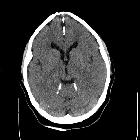

developmental and genetic origin affecting the paediatric craniofacial skeleton. Typical manifestations of nevoid basal cell carcinoma syndrome (NBCCS) in a 16-year-old boy. a Orthopantomography (OPT) shows cystic lesions of the mandible and maxilla (arrows), with unilocular and multilocular pattern and smooth or scalloped borders associated with displaced and unerupted permanent teeth. b Coronal CT scan (bone window) shows ectopic calcifications of the falx cerebri and tentorium cerebelli (arrows) and spotted meningeal calcifications (arrowheads). Brain MRI reveals a cavum veli interpositi on axial T2 (asterisk in c) and coronal contrast-enhanced T1 (asterisk in d) and also vermian dysgenesis (arrowheads in d)